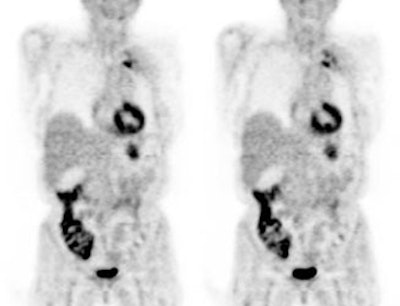

|

Metformin bowel activity: A large

amount of bowel activity can be seen in this patient

that was taking metformin. |